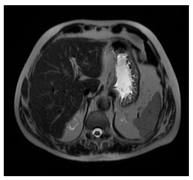

| MRI–T2 | ![]() | ![]() | ![]() |